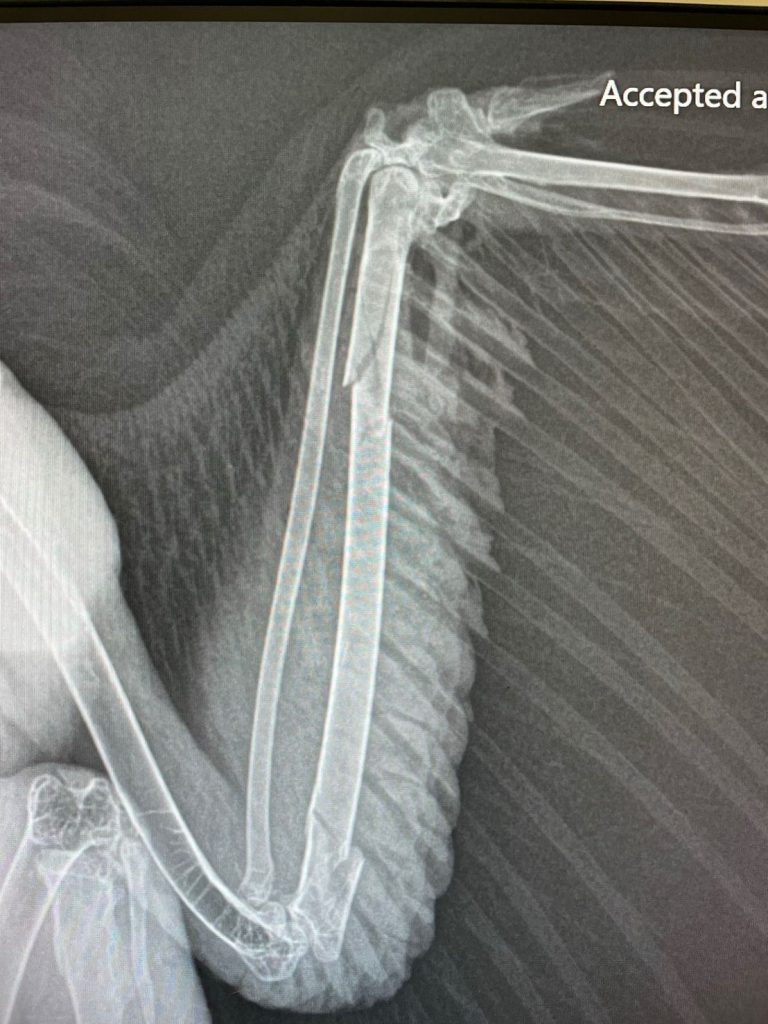

One such story is that of a red-shouldered hawk that was brought to us after being found injured. Upon arrival, we conducted a full intake examination, and it was immediately clear that something was wrong with his left wing. The way he held it close to his body, reluctant to extend it, signaled a serious injury. To confirm our suspicions, we took radiographs, which revealed the extent of his damage—his ulna was broken in two places, and his radius had been dislocated from the humerus bone.

Our team carefully stabilized the fractures and set the dislocation correctly, hoping that with time and proper care, he would regain full use of his wing. Over the next several weeks, the hawk rested and received daily medical attention, his diet carefully monitored to ensure he had the nutrition needed for bone healing. His ulna mended well, and he grew stronger, but despite our best efforts, it became clear that he would never be able to hunt effectively again.